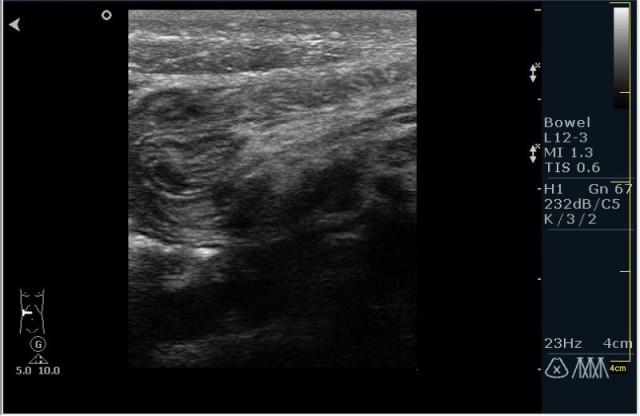

Ребёнок с болями в животе.

инвагинация! :!:

На представленных сонограммах определяется типичная "мишень" или "кокарда" (7ая и 8ая сонограмма сверху), которая при продольном сканировании превращается в "телескоп" (сонограммы 3 & 4). Все это указывет на инвагинацию кишечника (илео-цекальную). Причиной явилось лимфаденопатия брыжейки (которую вы указали). Увеличеные лимфоузлы вместе с инвагинатом хорошо различимы в просвете толстой кишки.

Уважаемые коллеги! Без сомнения имеет место илео-цекальная инвагинация.увеличенные овальные лимфоузлы, да еще такими гроздями характерны для мезаденита.Все зависит от развертывания клинической симптоматики.

Вариант 1- развите острого мезаденита спровоцировало инвагинацию.

вариант 2 - повторяющиеся эпизоды инвагинации привели к лимфоаденопатии.